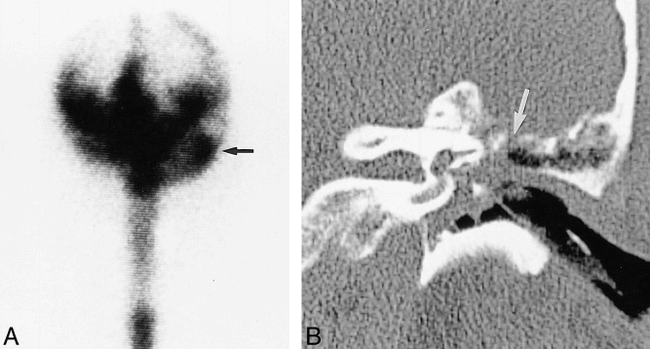

Patient with a defect revealed by CT and a leak revealed by radionuclide cisternography but not by CT cisternography.

A, Radionuclide cisternogram of the head, anterior planar view, shows an abnormal accumulation of radionuclide (arrow) in the left mastoid region.

B, Coronal CT scan of the temporal bone shows a defect (arrow) in the tegmen tympani with adjacent mucosal thickening. The bone and dural defect were confirmed at surgery.